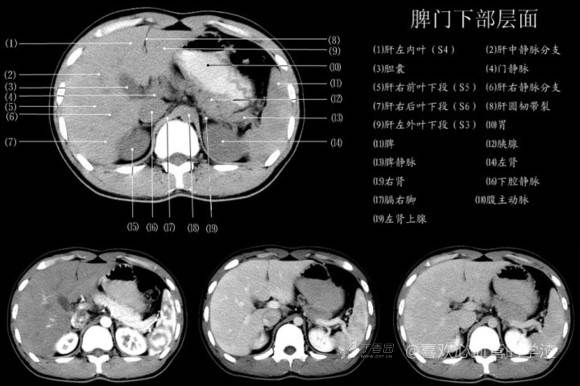

其实你离掌握上腹部 CT 影像只有一套高清实用图谱的距离,下面把我最喜欢的这本图谱分享给大家,为了方便阅读,我加了中文标识。后面附赠几张血管相对位置解剖关系图片,帮助大家理解(文中多图,建议在 wifi 环境下查看)。